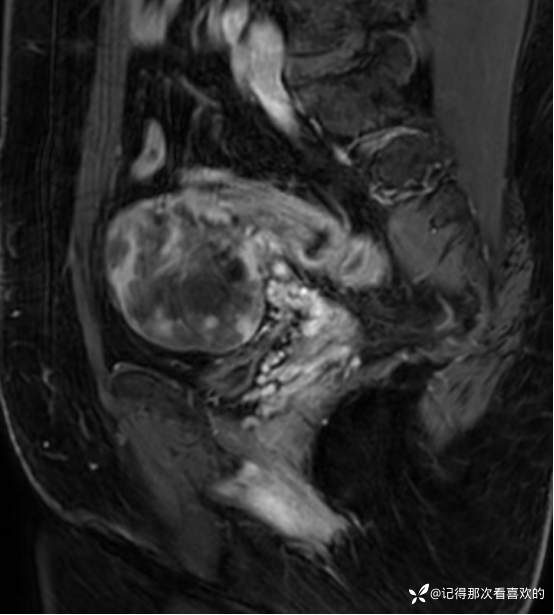

入院后查十二通道常规心电图:1、窦性心律2、逆钟向转位。余相关检验未见明显异常。于2025.05.30在静脉麻醉下行“宫腔镜诊断性刮宫术”,术顺,术后病理(2508387):(宫内容物)子宫内膜息肉。查心脏彩超(Z250530002):三尖瓣轻度反流。双侧下肢深静脉血管彩色多普勒超声(Z250530003):双侧下肢股总静脉反流,考虑双侧下肢深静脉瓣功能不全。经阴道彩超检查(Z250530004):双侧附件区低回声不均团块,考虑MT,建议进一步检查。子宫多发肌瘤。子宫内膜区低回声结节,考虑粘膜下肌瘤可能。宫颈腺体多发囊肿。盆腔MRI增强(MR109286):1.双侧附件区团块状占位,考虑MT,请结合临床。2.子宫肌层内、浆膜下多发肌瘤。3.子宫腔内异常结节灶,粘膜下肌瘤可能。4.盆腔少量积液。5.右侧髂骨内结节灶,性质待定,建议进一步检查。胸部CT(CT384707):1.双肺多发微小结节,建议随诊复查。2.气管憩室。3.扫及右肾结石?新上腹部CT平扫(CT384838):盆腔右侧占位性病变,请结合临床及MRI检查。HPV+TCT:HPV阴性;非典型鳞状上皮细胞(不能明确意义)。2025.06.03行胃肠镜,电子胃十二指肠镜检查(PG25003031):胃体溃疡(待病理);慢性萎缩性胃炎。电子结肠镜检查(PC25002608):结肠多发息肉(内镜下息肉切除+钳除)。快速石蜡病理(2508504):胃体:低分化腺癌,伴少量印戒细胞癌成分,免疫组化结果待补充报告。快速石蜡病理(2508505):降结肠:增生性息肉。